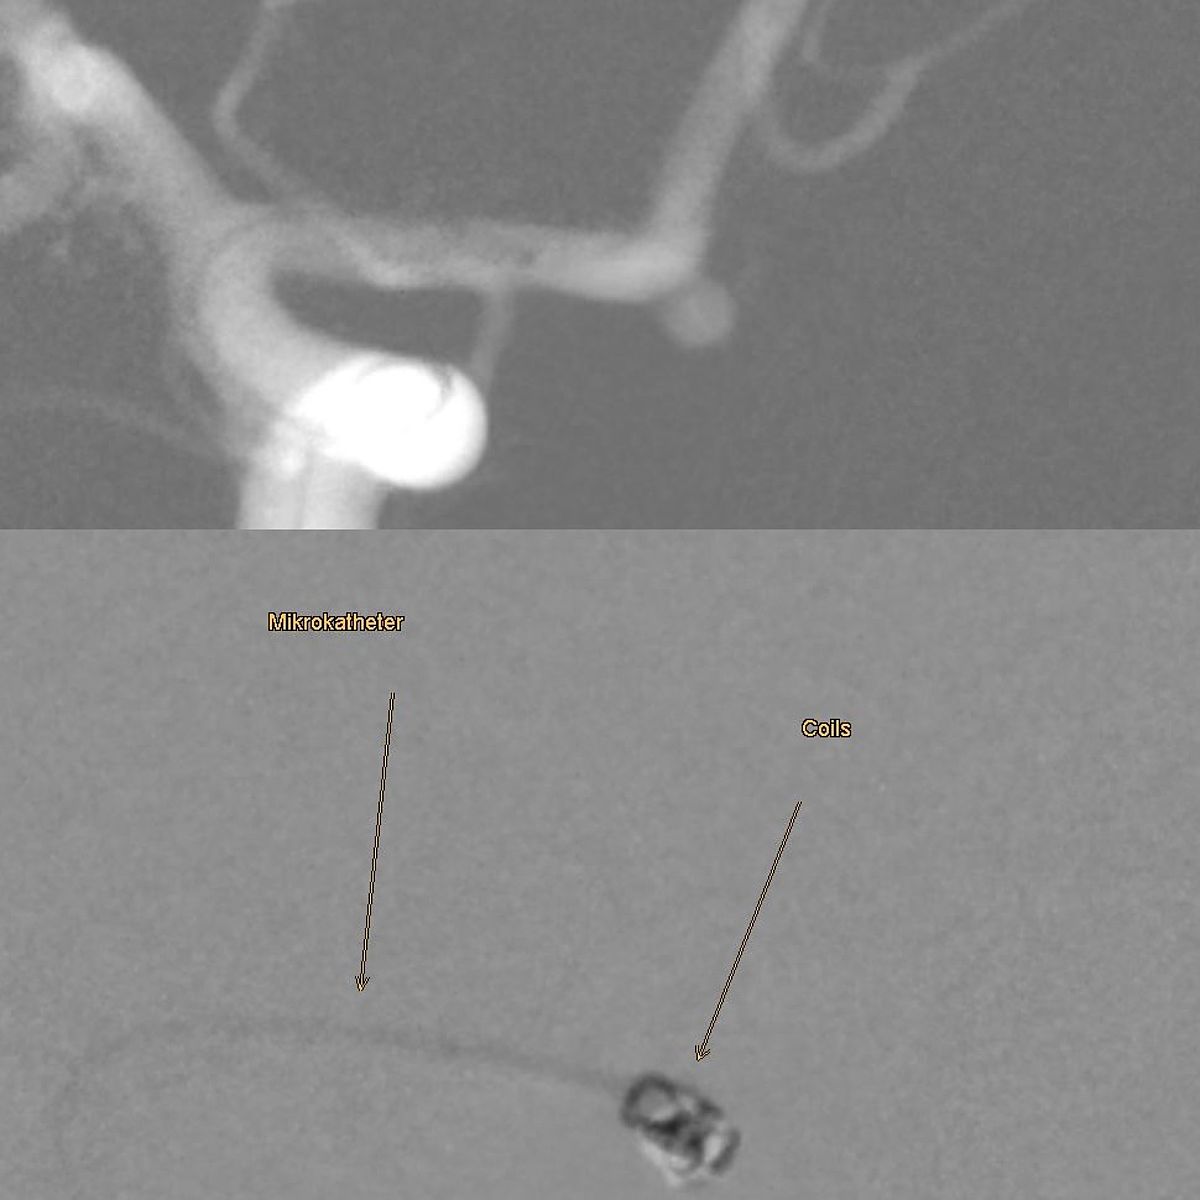

In Augsburg werden im Jahr etwa 80 solcher akuter Subarachnoidealblutungen behandelt. Dabei ist neben der Behandlung der Blutungsfolgen vor allem die Ausschaltung des ursächlichen Aneurysmas dringlich, was meist interventionell durch die Neuroradiologie erfolgt.

- Wie kann es behandelt werden?